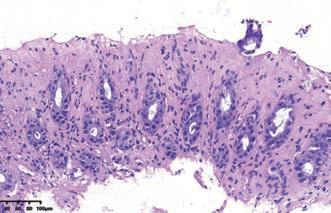

这种粘膜损伤的模式是指肠粘膜上半部隐窝萎缩、细胞体积变小,呈立方状、胞质黏液减少。可见隐窝细胞凋亡增多、隐窝枯萎(crypt withering/withered crypts)等表现。这种病理改变,多见于缺血性肠病、药物性肠炎、病毒感染等。

图解:炎症性肠病毒性/缺血黏膜损伤模式病理图(HE × 4 物镜)黏膜上半部隐窝萎缩,细胞变立方形,胞质黏液减少,黏膜固有层炎症细胞少,间质透明变,表面上皮脱落